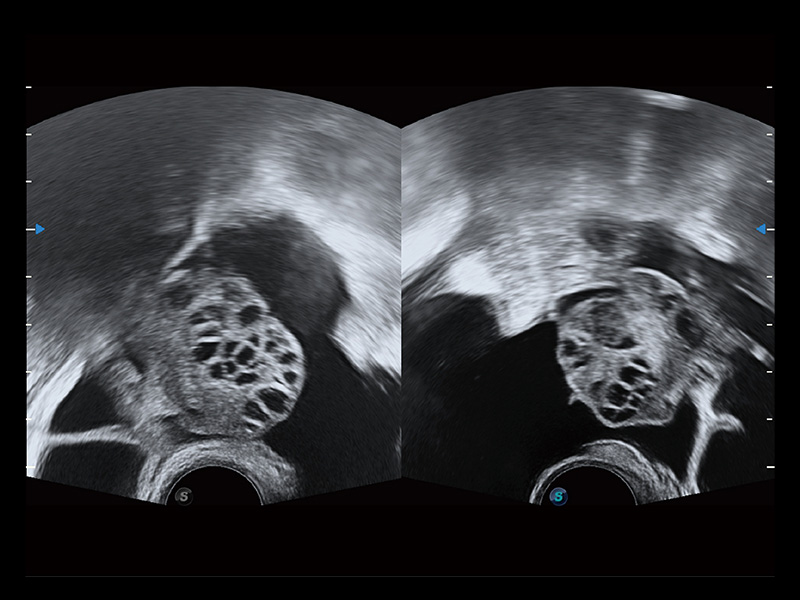

“生育问题”即关系民族复兴,也关系亿万家庭的幸福。随着婚育年龄推迟、社会压力增加等因素,越来越多人群也面临着“生不出、生不好”的问题。辅助生殖作为治疗不孕不育最有效的方法之一,也逐渐成为育儿新希望。而超声检查能为生殖需求人群的初诊评估提供宝贵的信息。 P20 Elite是玖鼎集团匠心打造的一款生殖应用型彩超。她继承玖鼎集团高端极光平台,突破性地将多款新型芯片及硬件模块进行整合,均衡了高端系统性能与小巧灵动机身。P20 Elite卓越的图像质量搭载专科探头,旨在为您提供全面的辅助生殖解决方案。

P20 Elite配备了丰富的生殖探头群和临床应用功能,在卵泡监测、穿刺取卵、胚胎移植、妊娠确认等领域,为生殖需求人群提供了新的临床机会,重新定义高端超声如何应用于生殖健康检查。